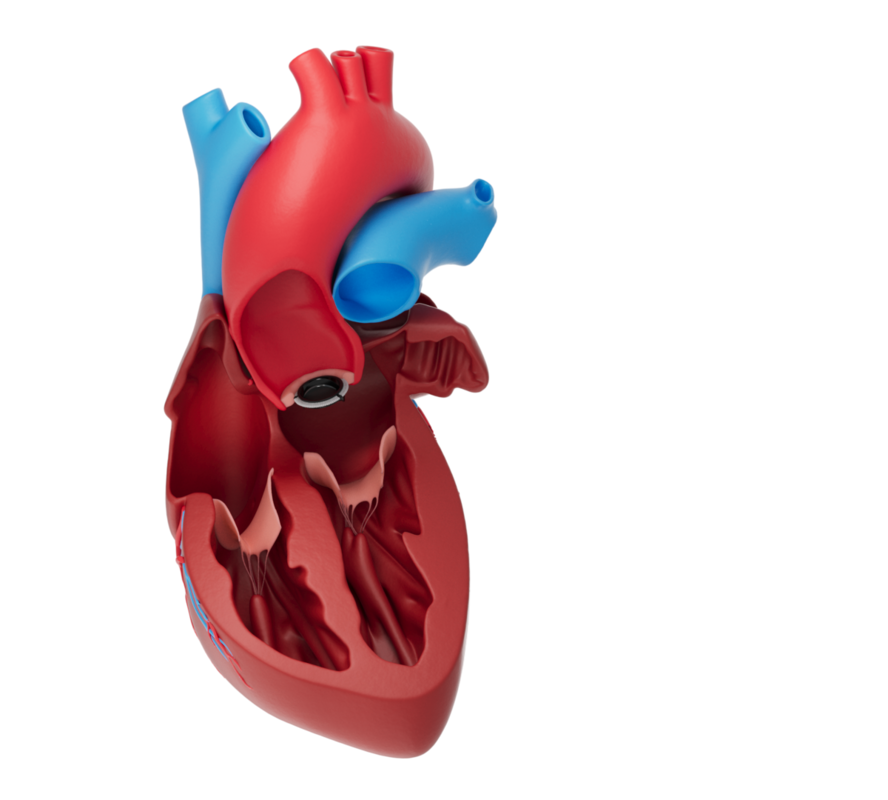

MECHANICAL HEART VALVE PROSTHESIS

Mechanical heart valves can take over the function of your body's own heart valves. They are generally made of so-called pyrolytic carbon. Like your own heart valve, the mechanical valve also has a ring that holds the valve leaflets in place. The mechanical valve opens and closes with every heartbeat so that the blood flows through the heart as desired.